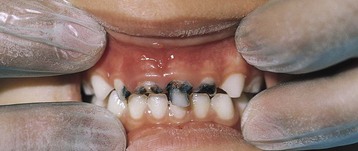

Early childhood caries (ECC), often called “baby-bottle tooth decay,” describes a caries pattern in the maxillary anterior teeth of infants and young children. Characteristics include rapidly developing carious lesions in the primary anterior teeth and the presence of lesions on tooth surfaces not usually associated with a high caries risk. Because tooth decay remains a common oral disease of childhood, caries are a primary marker for a child’s oral health. Good behavioral habits and child nutrition patterns must be encouraged, beginning in infancy.

Often ECC follows prolonged bottle-feeding, especially at night, of juice, milk, formula, or other sweetened beverages. The extended contact time with the fermentable carbohydrate–containing beverages, coupled with the position of the tongue against the nipple, which causes pooling of the liquid around the maxillary incisors, particularly during sleep, contributes to the decay process. The mandibular anterior teeth are usually spared (Figure 26-3) because of the protective position of the lip and tongue and the presence of a salivary duct in the floor of the mouth. In general, children from low-income families and minority populations experience the greatest amount of oral disease, the most extensive disease, and the most frequent use of dental services for pain relief; yet these children have the fewest overall dental visits (CDC, 2010).

Management of ECC includes diet and oral hygiene education for parents, guardians, and caregivers (Zero, 2010). Messages should be targeted to counter the health habits that contribute to this problem: poor oral hygiene, failure to brush a child’s teeth at least daily, frequent use of bottles filled with sweetened beverages, and lack of fluoridated water. Dietary guidelines include removal of the bedtime bottle and modification of the frequency and content of the daytime bottles. Bottle contents should be limited to water, formula, or milk. Infants and young children should not be put to bed with a bottle. Teeth and gums should be cleaned with a gauze pad or washcloth after all bottle feedings. All efforts should be made to wean children from a bottle by 1 year of age. Educational efforts should be positive and simple, focusing on oral hygiene habits and promotion of a balanced, healthy diet. Between-meal snacks should include cariostatic foods. When foods are cariogenic, they should be followed by tooth brushing or rinsing the mouth. Parents and caregivers need to understand the causes and consequences of ECC and how they can be avoided.